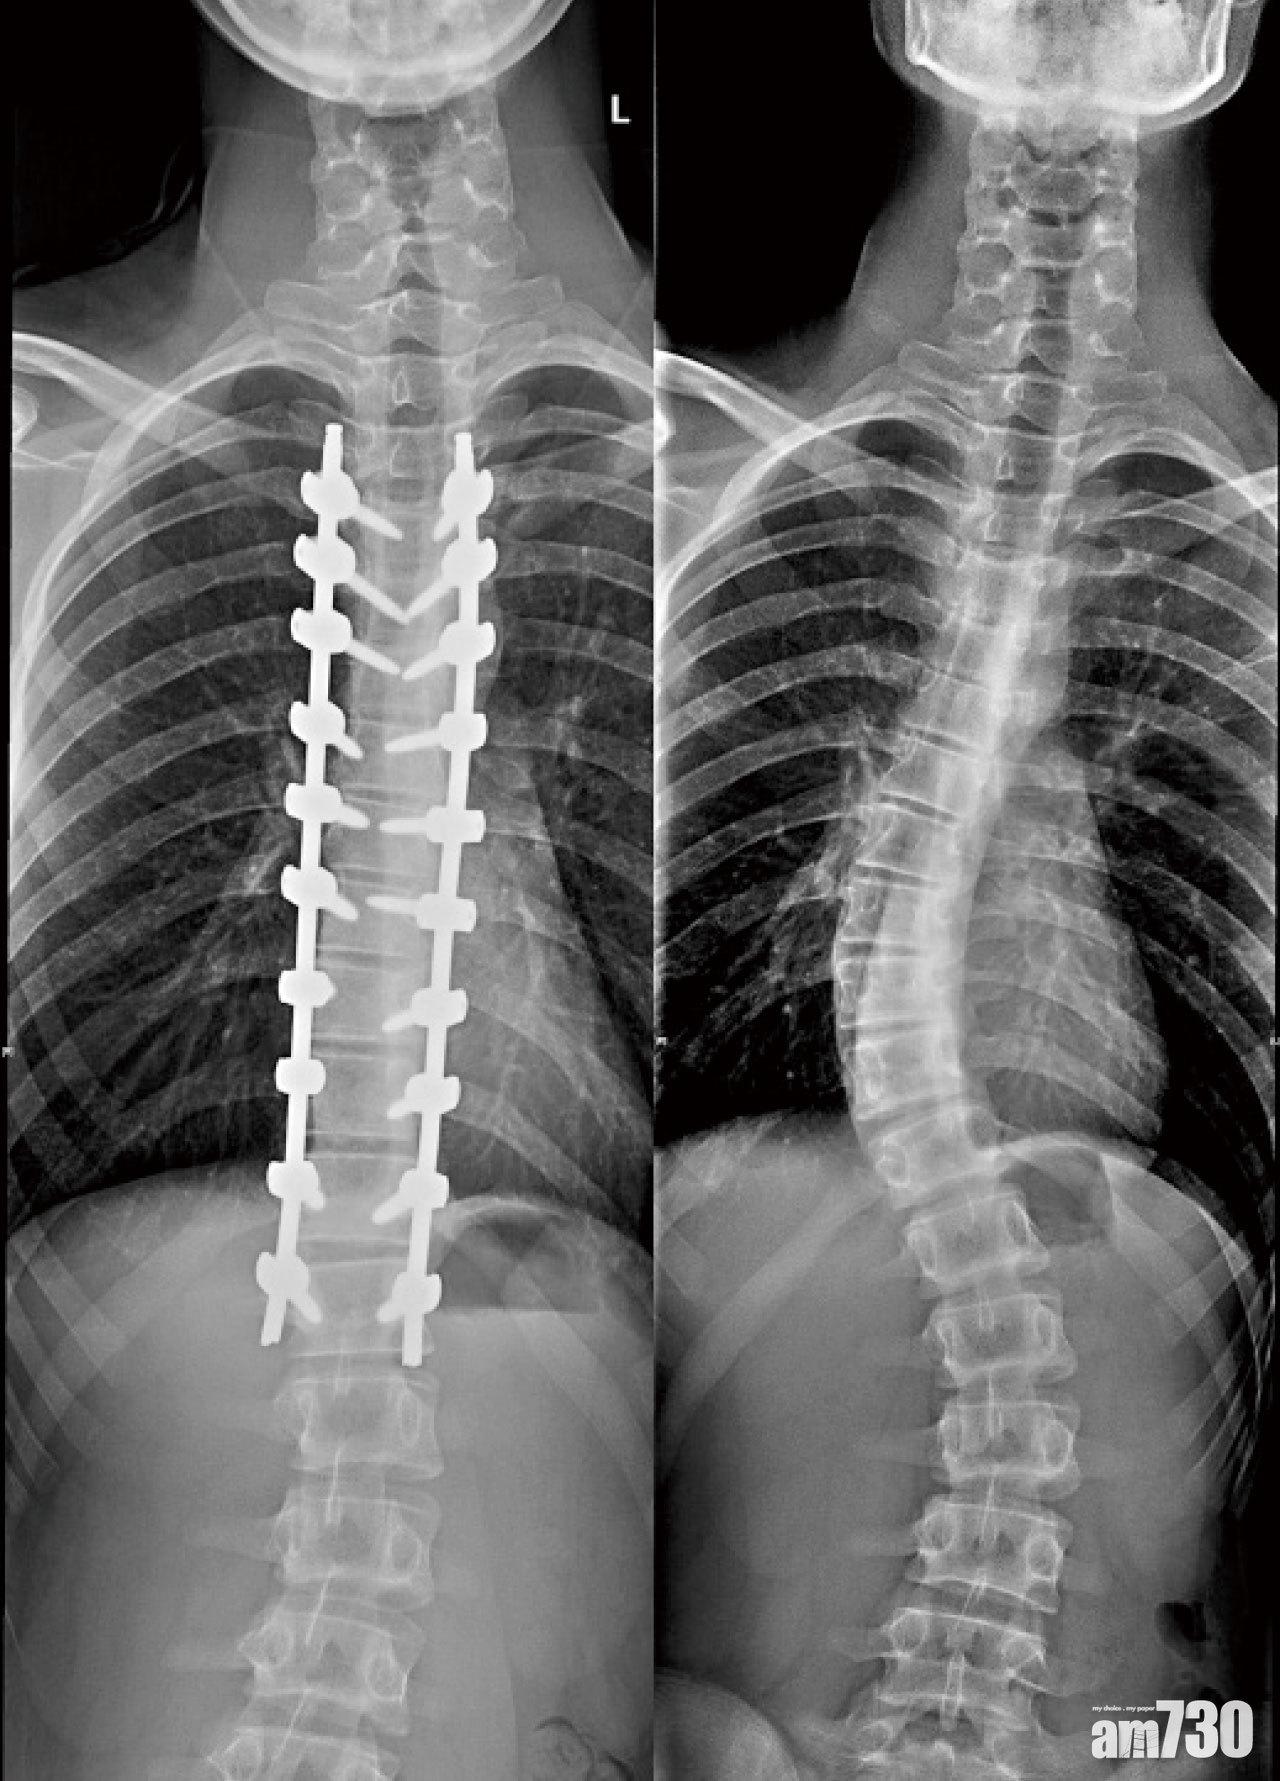

以手術固定脊椎,亦即在體內裝設鋼條與鎖上螺絲矯正彎曲的脊椎一段時間後,讓支撐的結構與骨頭融合以穩固骨骼,周邊或是手術切開範圍的肌肉容易產生痙攣、萎縮甚至沾黏,也會影響身體的活動性。而沒有固定的脊椎關節,需要幫忙更多的關節活動,長久下來容易因過度使用,使得沒有固定的區域提早退化,產生神經壓迫問題。